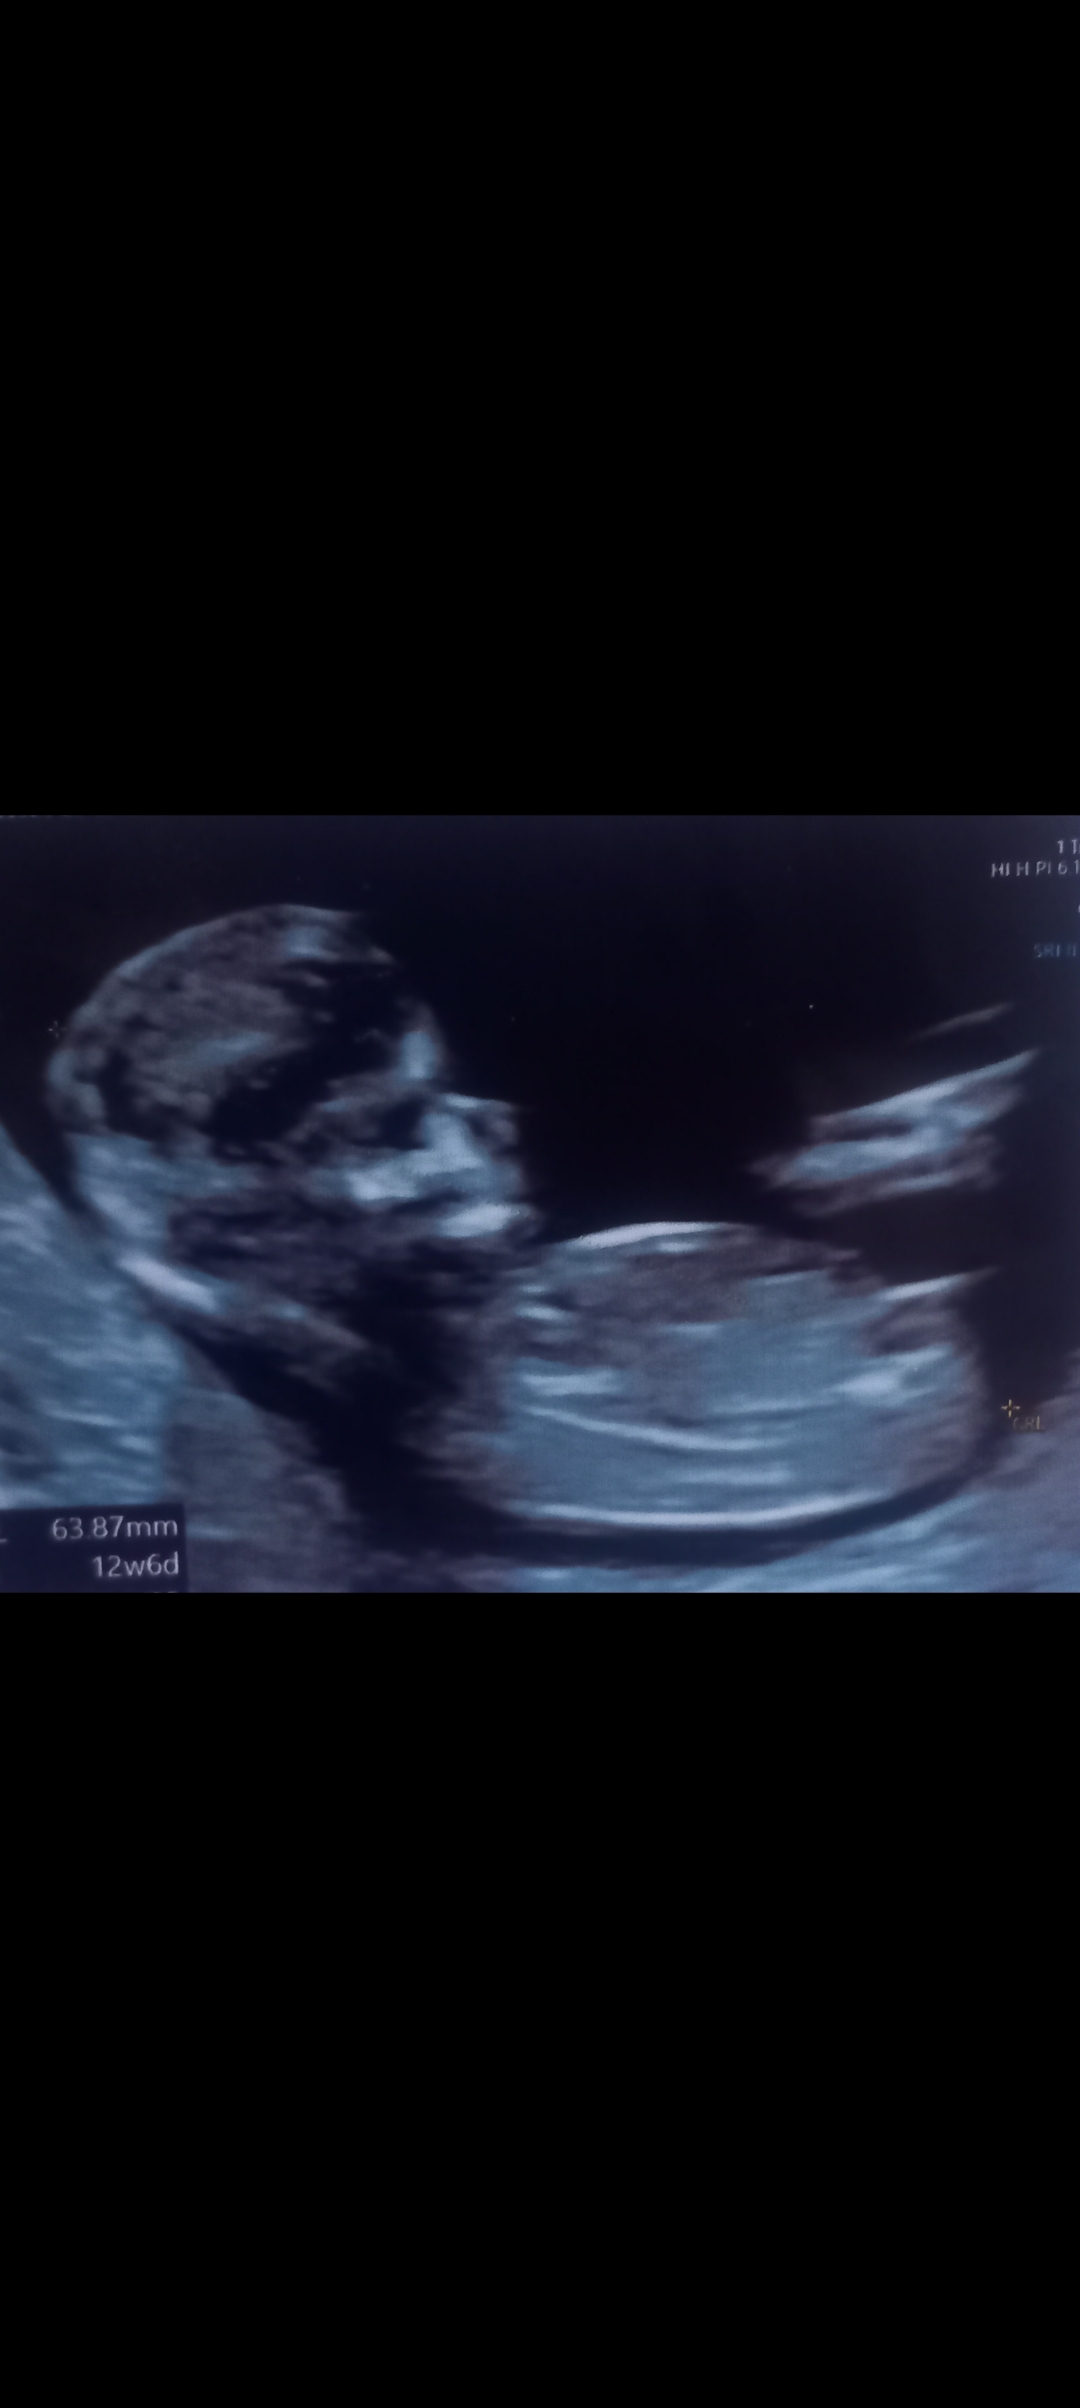

تعداد ضربان قلبش رو در سونو اول که رفتی واسه قلب و هفته بارداریت رو بگو با دقت ۹۰. درص بگم

واقعا نوددرصد ؟؟؟مال منم بذارم میگید

اره بگو تعداد ضربان قلب واینکه در کدام هفته این مهمه

140

تو هفته چند ۱۴۰ بود؟

7هفته و2روز

بنظر من دختر